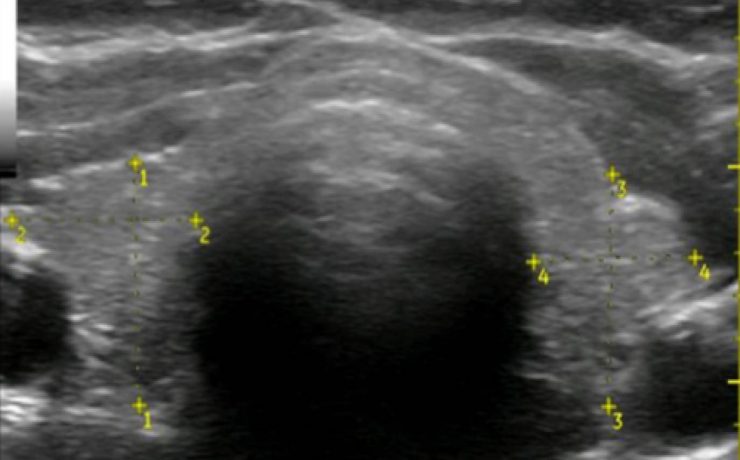

Las vías biliares intrahepática transcurren adyacentes a las raíces de la vena porta y las ramas de la arteria hepática. Los conductos hepáticos derecho e izquierdo se unen para formar el conducto hepático común a nivel del hilio hepático, el cual mide aproximadamente 30mm de longitud y se une al